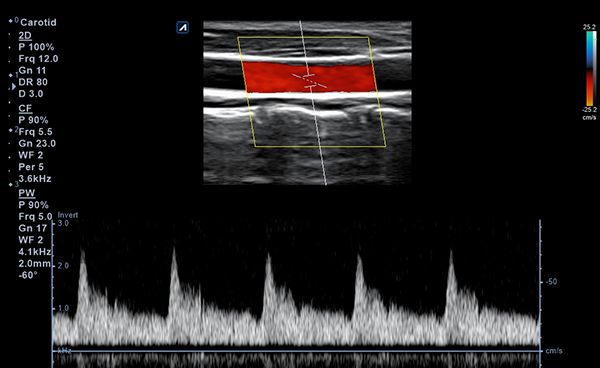

Alpinion Medical Systems, la empresa de sistemas de ultrasonido, ha combinado tecnologías

de procesamiento de imágenes y transductores para garantizar que minisono proporcione

imágenes 2D de alta definición e información de Doppler más claras y nítidas.

minisono ofrece funciones esenciales con el nivel de rendimiento necesario

para garantizar que los exámenes y diagnósticos sean precisos.

- Imaging modesB-mode, CF, M, PW, PD

- Frequency3-12 MHz

- Dimension (height/width/depth)25.2 / 62.5/ 150mm

- Weight 175g

- Field of view 38.4mm

- Max depth10 cm

- DisplayMicrosoft Surface

- Battery300 min